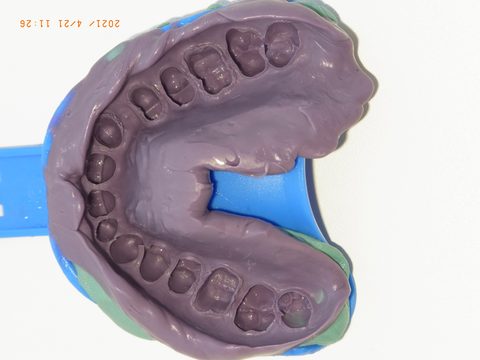

Gesamtansicht der fertigen Zweitabformung: vollständige Erfassung des Oberkiefers. Die beiden unabhängigen Abformungen erlauben dem Labor das Umsetzen zwischen den Modellen und decken Abformfehler frühzeitig auf.